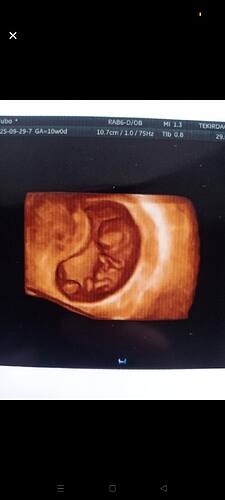

Sizce ney ![]()

![]()

Kese sekli gozukmuyor ki yakından kafa gozukuyor sadece. Uzaktan var mi